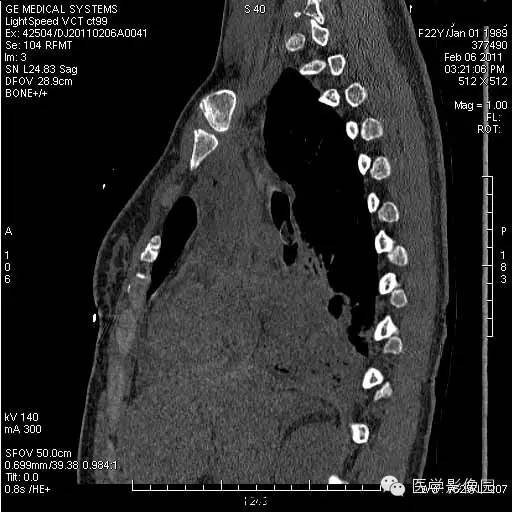

【病例】支气管异物1例CT影像表现

女,22岁,食用开心果后咳嗽不适。

管支气管异物是临床常见急症。异物可存留在喉咽腔、喉腔、气管和支气管内,引起声嘶、呼吸困难等,右支气管较粗短长,故异物易落入右主支气管。75%发生于2岁以下的儿童。CT三维重建清晰直观的显示异物的大小、位置,并能观察肺组织内是否有病变。